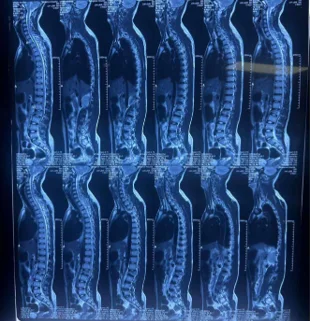

Before & After Clinical Gallery

We showcase real patient cases (with consent), including:

- Pre- and Post-operative MRIs and X-rays

- Disc Herniations, Stenosis, and Spondylolisthesis cases

- Visible improvement in alignment and decompression